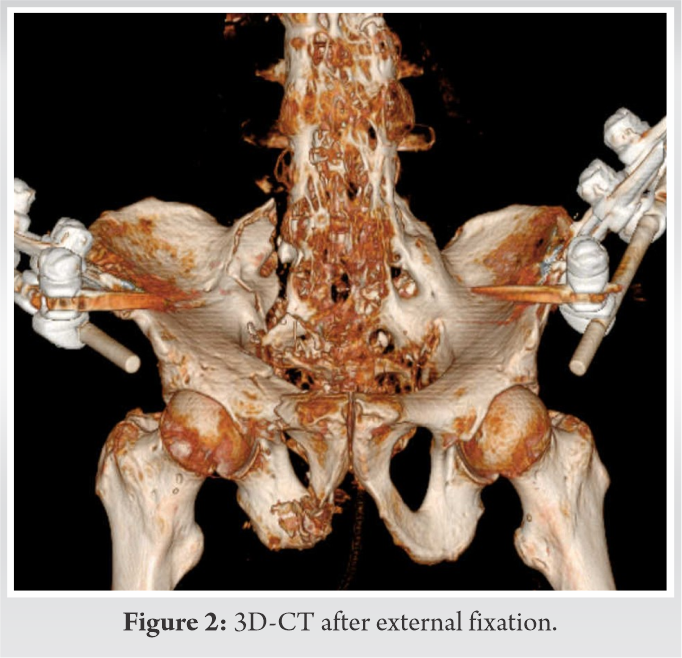

A 95-year-old male fell from the 2nd floor and presented with severe low back pain. An X-ray showed a pelvic fracture and ankylosis of the lumbar spine due to DISH (Fig. 1a, b). Computed tomography (CT) showed an unstable pelvic injury (AO type C2) with unstable sacral and pubic fractures on the right side, a stable sacral fracture on the left side, and bilateral ankylosis of the sacroiliac joints (Fig. 1c).

This patient also sustained a cerebral subarachnoid haemorrhage accompanied by a moderate consciousness disorder. Because of hypovolemic shock due to active bleeding from the common iliac arteries bilaterally, as detected on contrast-enhanced CT, and an unstable fracture, transcatheter arterial embolization, and external fixation of the pelvis were performed on the day of the injury (Fig. 2).